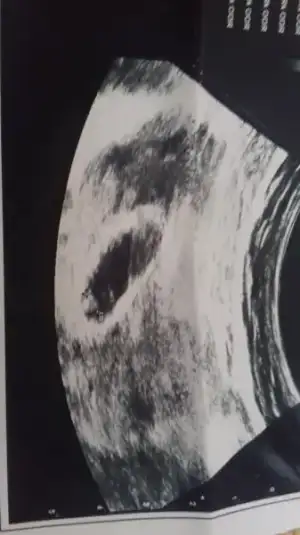

Merhaba kızlar bizde 11+4 olduk nasipse cinsiyet için doktor daha erken dedi ama tahminlerinizi yazarsanız çok sevinirimmm :anneadayı::KK200::emir_bebek:

• image.webp

image.webp

22,1 KB · Görüntüleme: 69